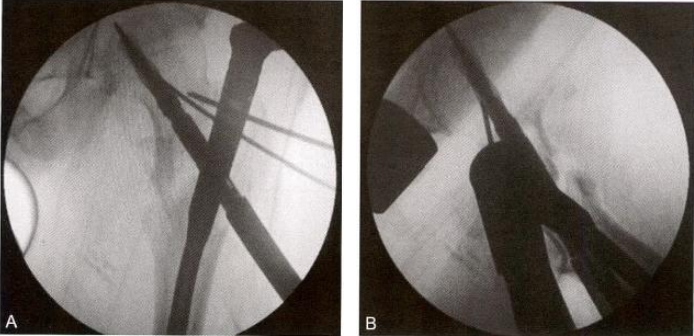

3)术中复位技巧3:点状复位钳钳夹固定(冠状位股骨转子间骨折)。 股骨大转子骨折线从前上方向后下方延伸,臀中肌的大部分位于近断端,臀中肌的前份在大转子的止点位于远断端,后方软组织铰链破裂,呈现骨折端后方张口,股骨颈及相连的大转子大部呈现极度外旋(图 9-10A 、B 、C)。先将远端外旋牵引,同时用点状复位钳钳夹,使骨折后方张口复位,然后经大转子后方植入克氏针,改内旋、内收牵引,在大转子顶点插入 导针,常规开口扩髓,植入主钉和螺旋刀片(图9-10)。

图9-10 点状复位钳夹固定。 A.术前X 线 ;B. 术前CT 正位;C. 术前CT 侧位;D. 钳夹复位后侧位透视